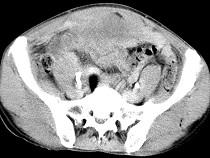

问题 男,56岁,无规律上腹痛,左锁骨上淋巴结肿大,消瘦、乏力,影像检查如图,最可能的诊断是()

选项 A.腹膜结核 B.胃溃疡穿孔 C.胃癌并盆腔种植 D.胃及腹腔淋巴瘤 E.肠系膜淋巴管瘤

答案 C